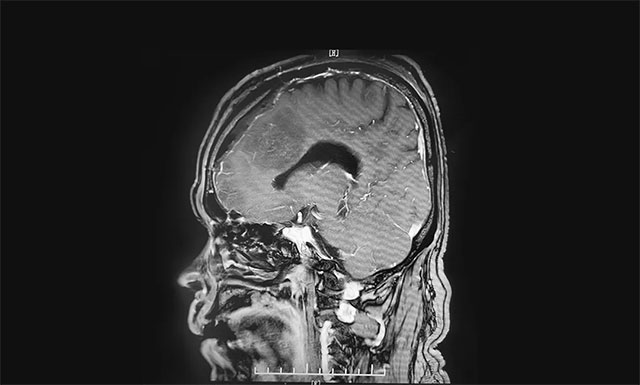

▲ 术后影像显示肿瘤被切除

术中可见肿瘤起源于大脑镰并跨越两侧,在显微镜下,李士其教授在吴治群博士、黄秀夫医生及医护团队协助下,凭借精湛的手术技巧和丰富的临床经验对肿瘤进行精细剥离。在充分保护好上矢状窦、中央区的静脉回流的前提下,经过5个多小时的手术,最终肿瘤被顺利切除。术后的病理结果显示是良性脑膜瘤。